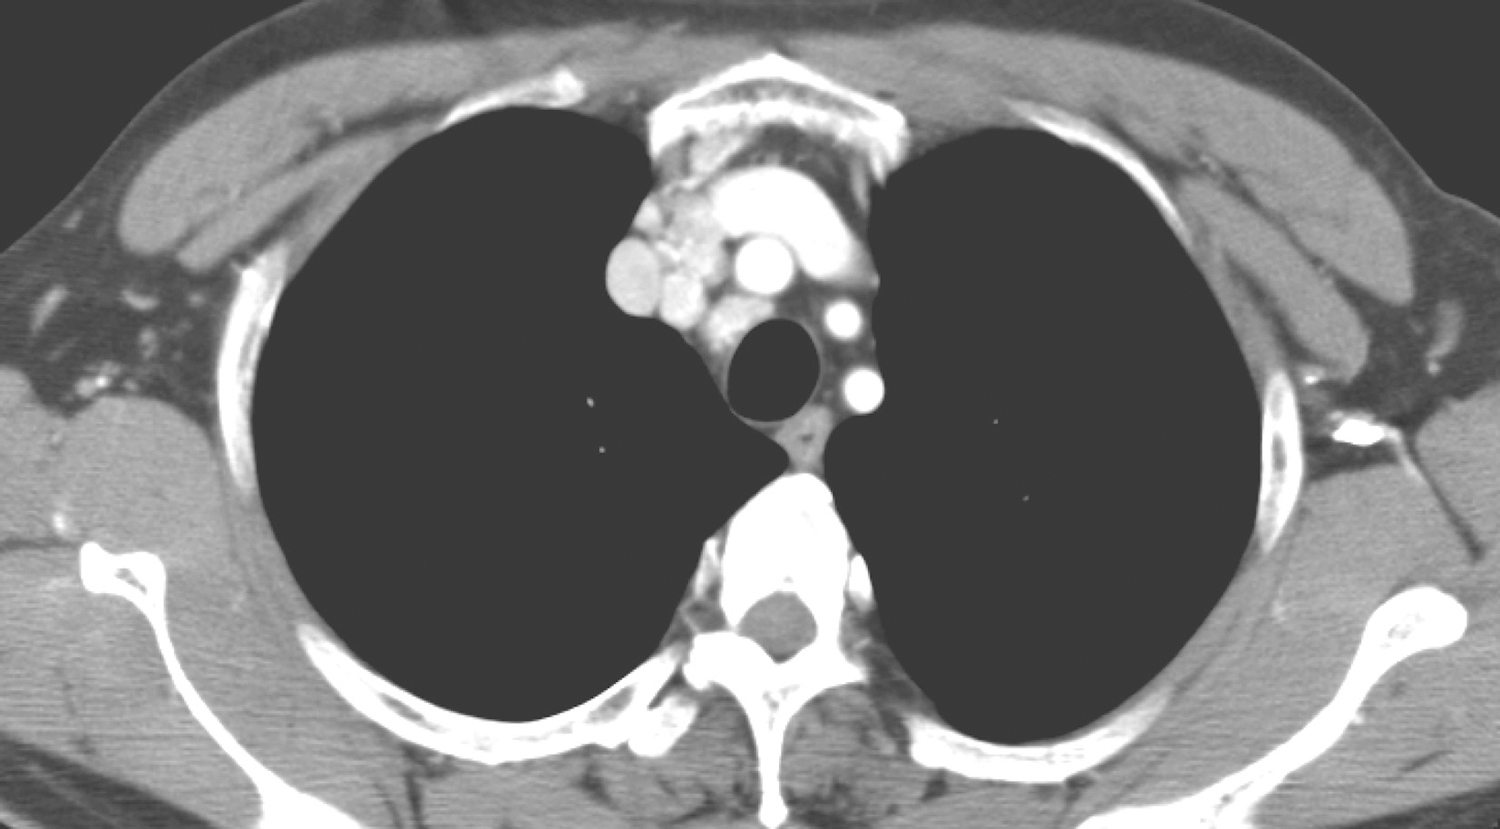

双肺多发小结节,较大者约0.6cm,边界光整。余双肺野未见明确异常。

(3)双肺多发转移瘤。